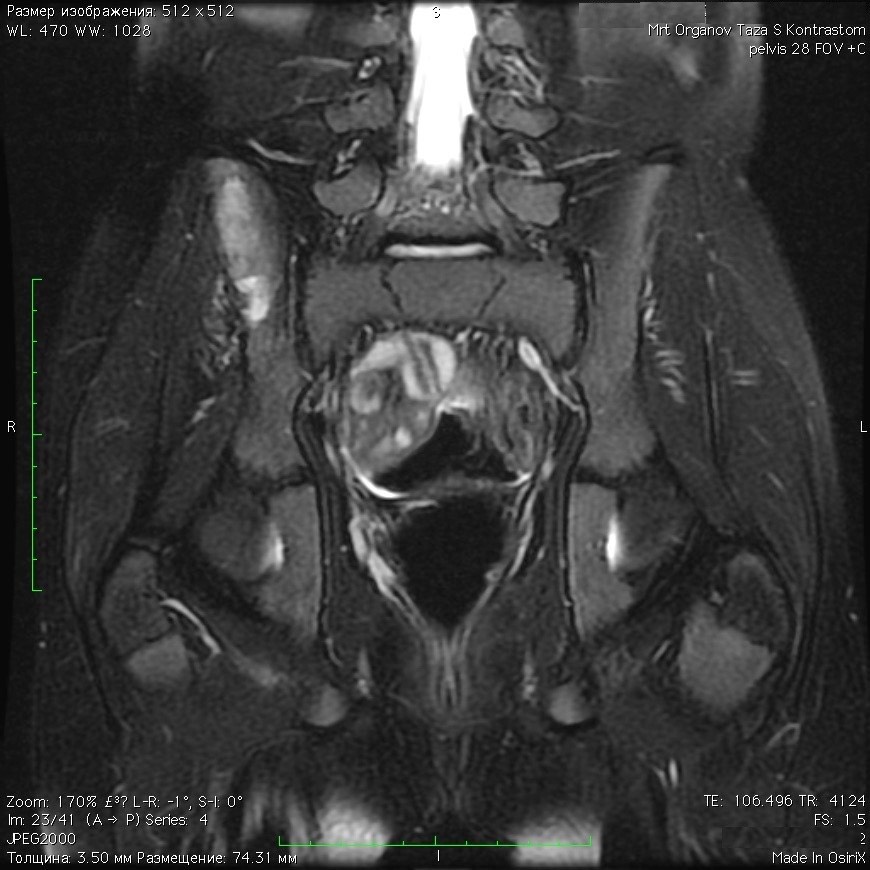

1329. Мальчику 12 лет с жалобами на образование в области ягодицы (других жалоб не предъявляет) выполнена магнитно-резонансная томография, заболеванием, которое может соответствовать клинико-рентгенологической картине, считают